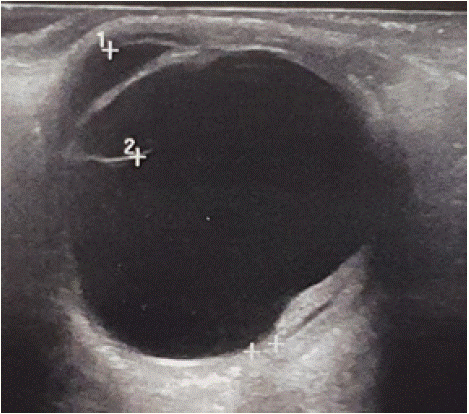

In the left eye, the findings on OCT angiography were obscured by hemorrhage and did not allow clear CNV demonstration. The spectral domain OCT (SD-OCT) of the right eye did show juxtafoveal CNV with associated subretinal fluid and hyperreflective dots (Figure 4). B-wave echo of the left eye shows extensive subretinal hemorrhage (Figure 5)

Figure 4: The spectral domain OCT (SD-OCT) of the right eye did show

juxtafoveal CNV with associated subretinal fluid and hyperreflective dots.

Figure 5: B-wave echo of the left eye shows extensive subretinal

hemorrhage.